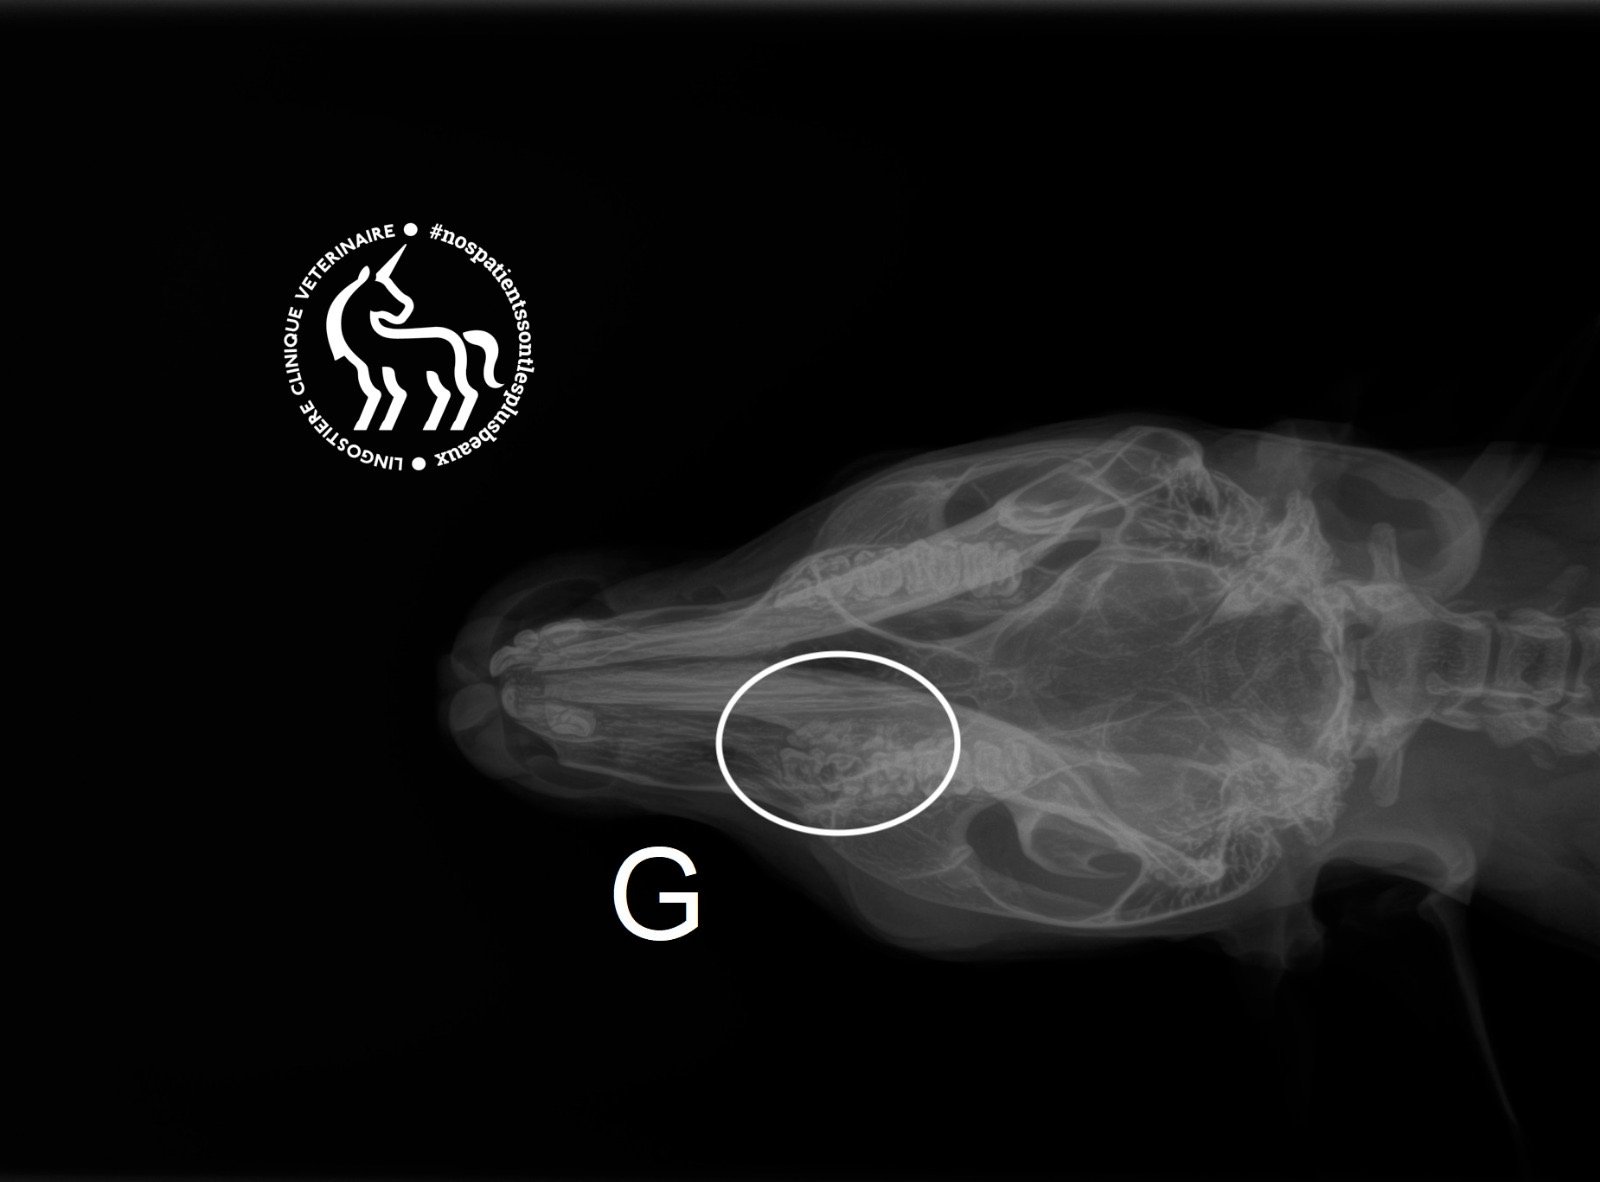

- radiographies (traumatologie, fractures),